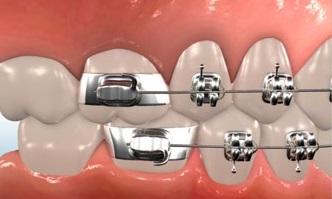

Bite turbos are small platforms placed on the inside of the upper front teeth, to prevent full closure of the teeth. When upper and lower braces are placed at the same time, the top teeth bite down and contact the lower braces. These are placed when a person has a very deep bite where if bite turbos where not placed they would be able to bite the lower brackets off.